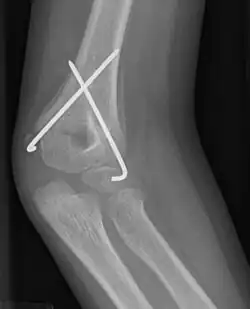

![]() Supracondylar humeral fracture, treated with closed reduction and pinning | |

Percutaneous pinning is a technique used by orthopedic and podiatric surgeons for the stabilization of unstable fractures. Percutaneous pinning involves inserting wires through a person's skin for stabilizing the fractured bone.[1]

Numerous pinning techniques have been proposed, however there is not enough evidence to determine which is more effective.[1] Pinning involves the manipulation, with X-ray guidance, of the fracture into an acceptable position, and the immediate insertion of metal pins, called Kirschner wires, through the skin, into one bone fragment and across the fracture line into the other bone fragment. These pins are normally left in position for some four to six weeks, and are removed when the fracture has healed.